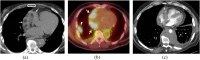

The objectives of this article were: (1) to review common and rare manifestations of systemic and pulmonary Langerhans cell histiocytosis, Rosai-Dorfman disease, Erdheim-Chester disease and juvenile xanthogranuloma; (2) to provide the reader with important pathologic, epidemiologic and clinical features of these diseases. The histiocytoses are a diverse group of diseases which typically manifest with multiorgan involvement. Understanding the pathologic, epidemiologic and clinical features of these entities can help the radiologist suggest an accurate diagnosis of histiocytosis when typical imaging features are encountered.